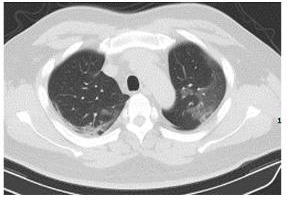

With COVID-19 tests being carefully rationed out and there being multiple scarcities, patients may not have access to a traditional test. Our software can diagnose a patient purely on a CT scan, eliminating the need for single use tests. We used the COVID-19 Lung CT Scans by LuisBlanche on Kaggle.

Our web app has a form for submitting patient data and uploading a CT scan image. We then pass the pixel data to our server, which runs several Tensorflow models. We then take the average confidence of all the models, and return the prediction to the browser. You can test it with the CT Scan images in the Devpost Gallery.

We built 8 Deep Learning Models with Tensorflow and Keras that integrate convolutional neural network architecture and was trained using K-fold Cross-validation, in order to make best use of a limited dataset. Our model achieved nearly 90% accuracy, allowing hospitals to use this as a tool to diagnose patients when resources are limited.